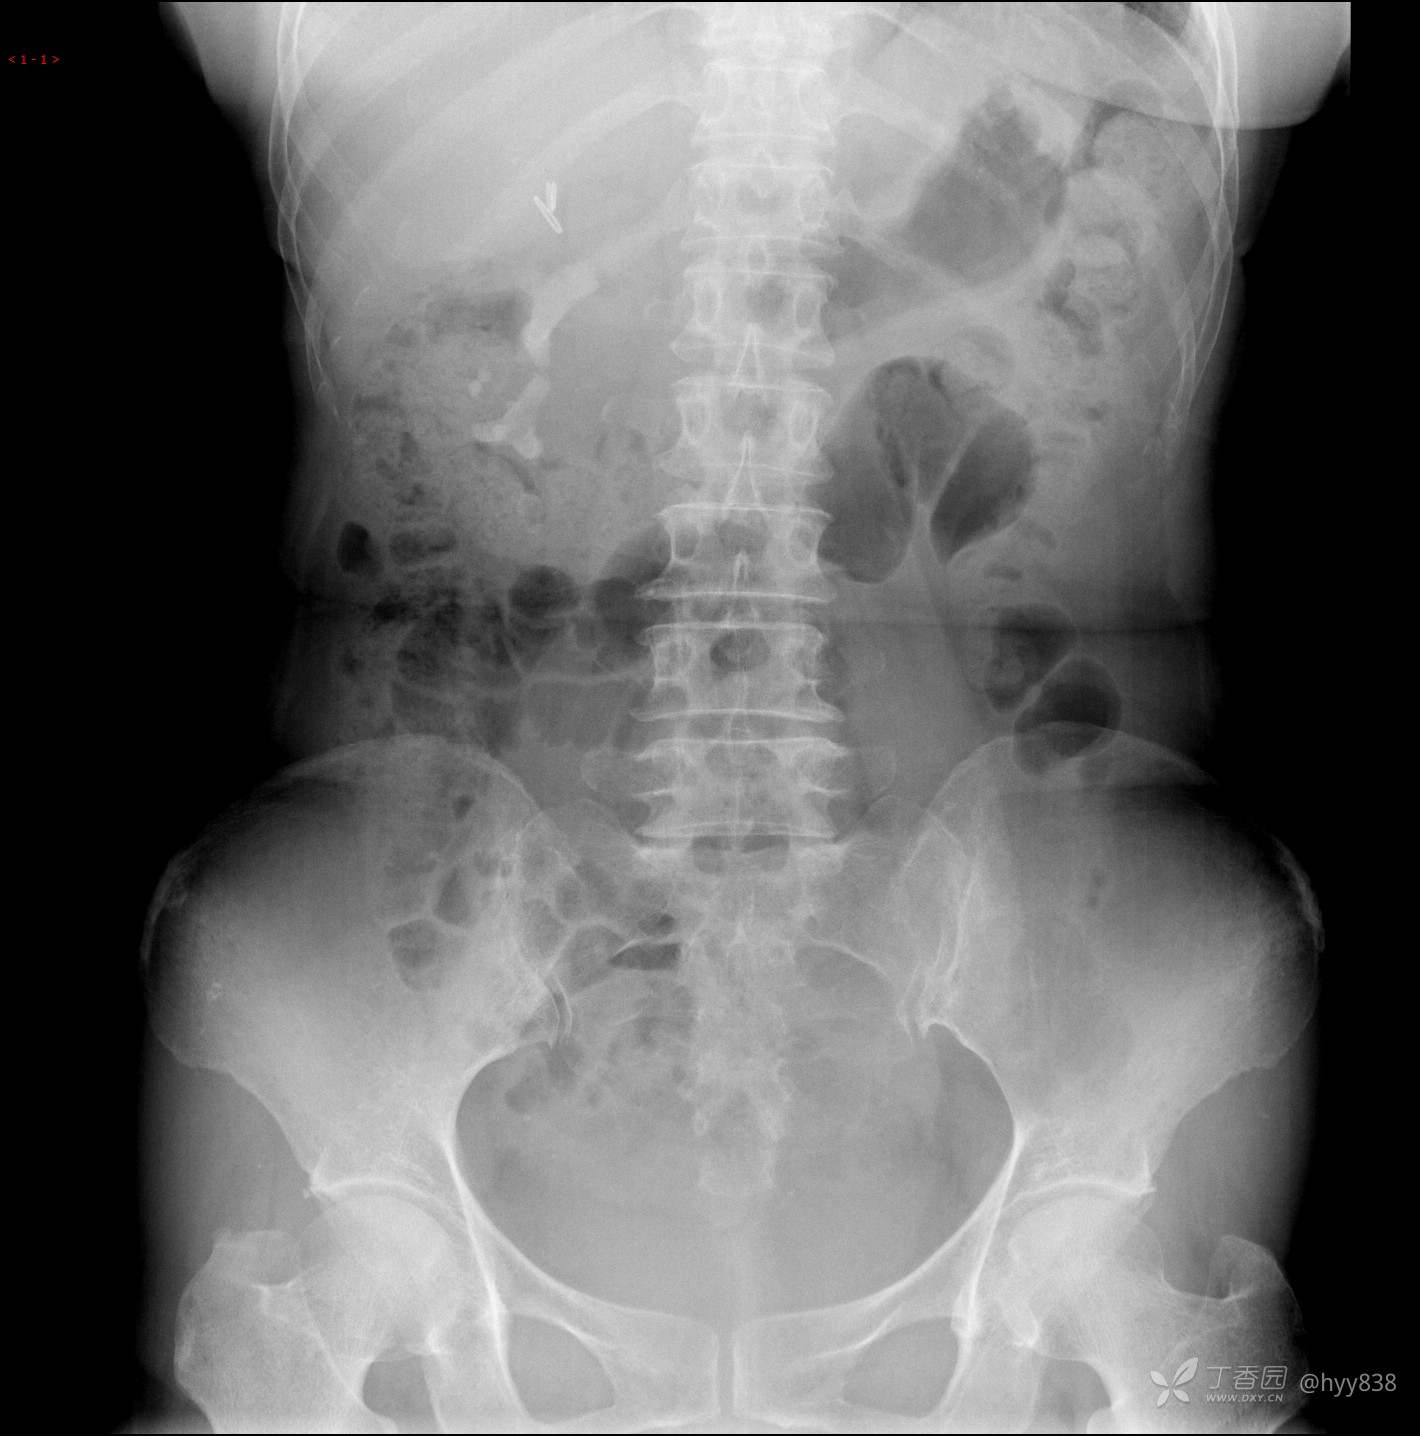

平片